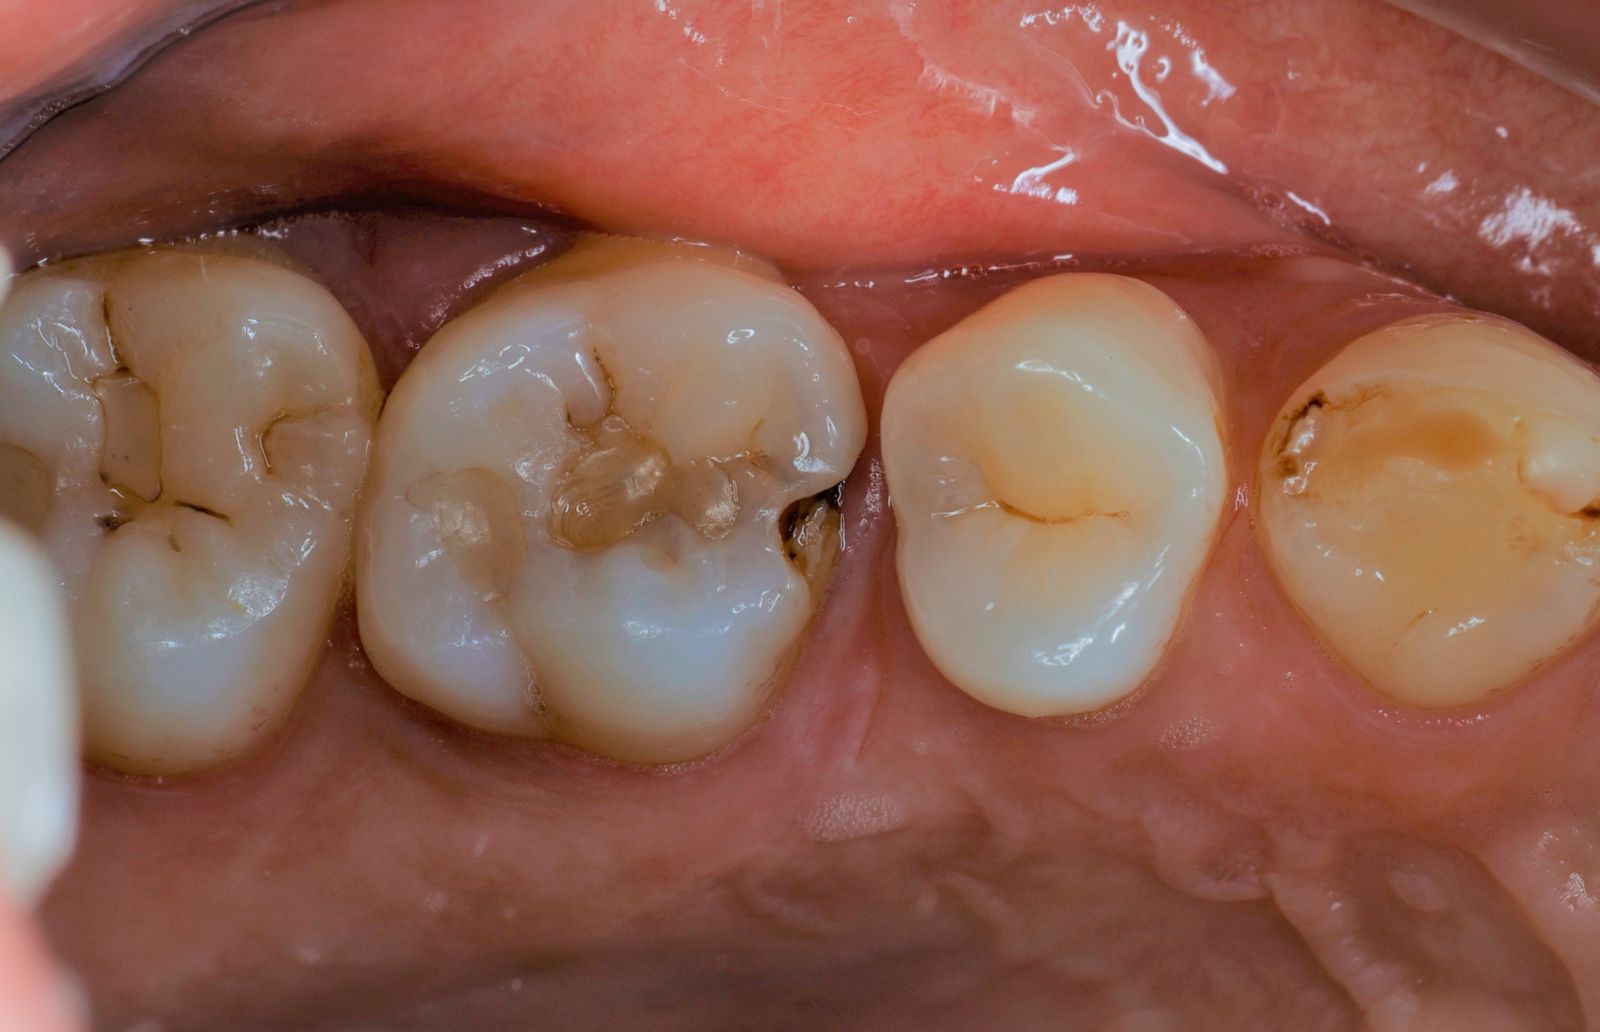

【 案 例 四】